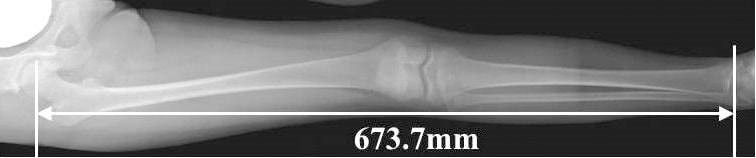

Providing super high accuracy measurements

SLOT Advance collimates the X-ray beam, so that it only exposes a narrow central slit field without distortion caused by oblique rays. These central slit images are captured using the SONIALVISION's super-high resolution Flat Panel Detector (FPD) by moving it in parallel with the X-ray tube. These successive images are then automatically reconstructed to create one long image in SONIALVISION G4's digital imaging unit (DR-300).

Therefore, this enables very high accuracy measurements without distortion, even with a very simple workflow.

Accurate measurements

CR stitching